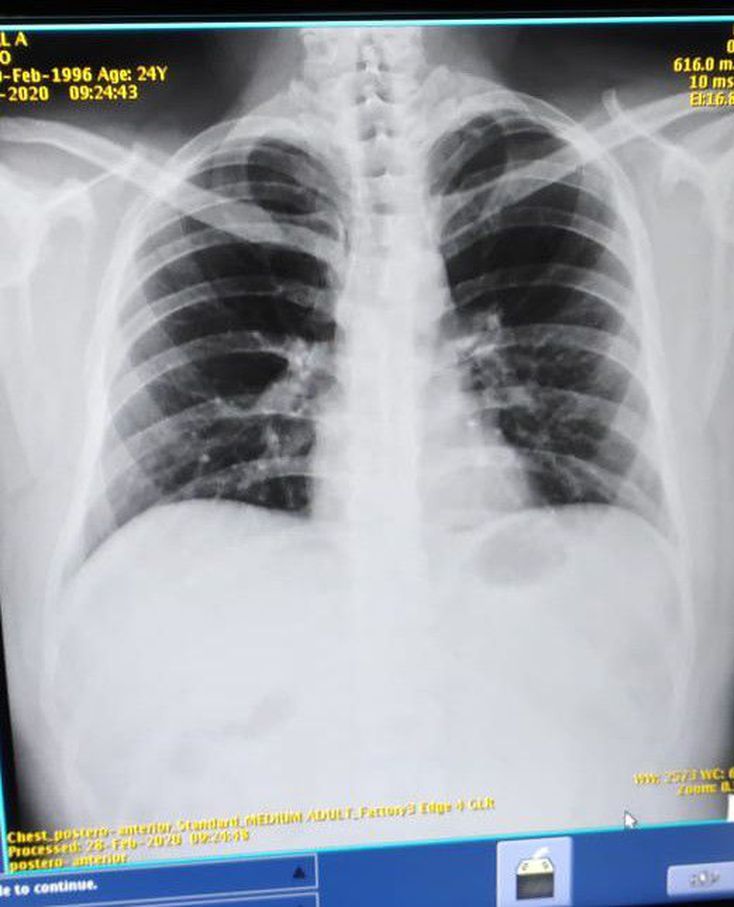

Diagnosis?

Trachea shift towards left side .It may be a case of left side fibrosis of lungs